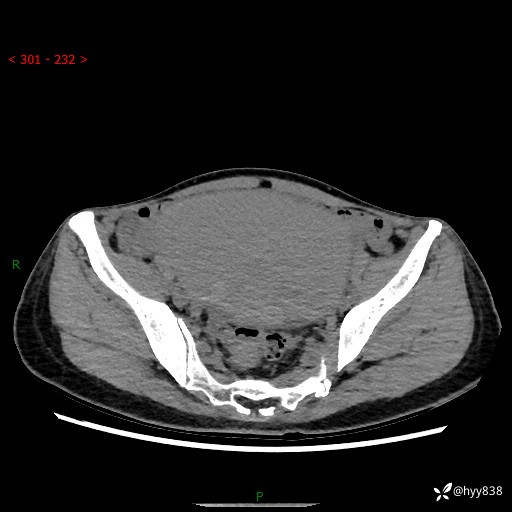

【患者信息】:女,50岁

【主诉】:外院超声发现腹盆肿块,为进一步诊治来我院,门诊已“盆腔肿块”收入院。

腹盆CT平扫+增强

【临床诊断】:盆腔肿瘤

【治疗经过及结果】:手术